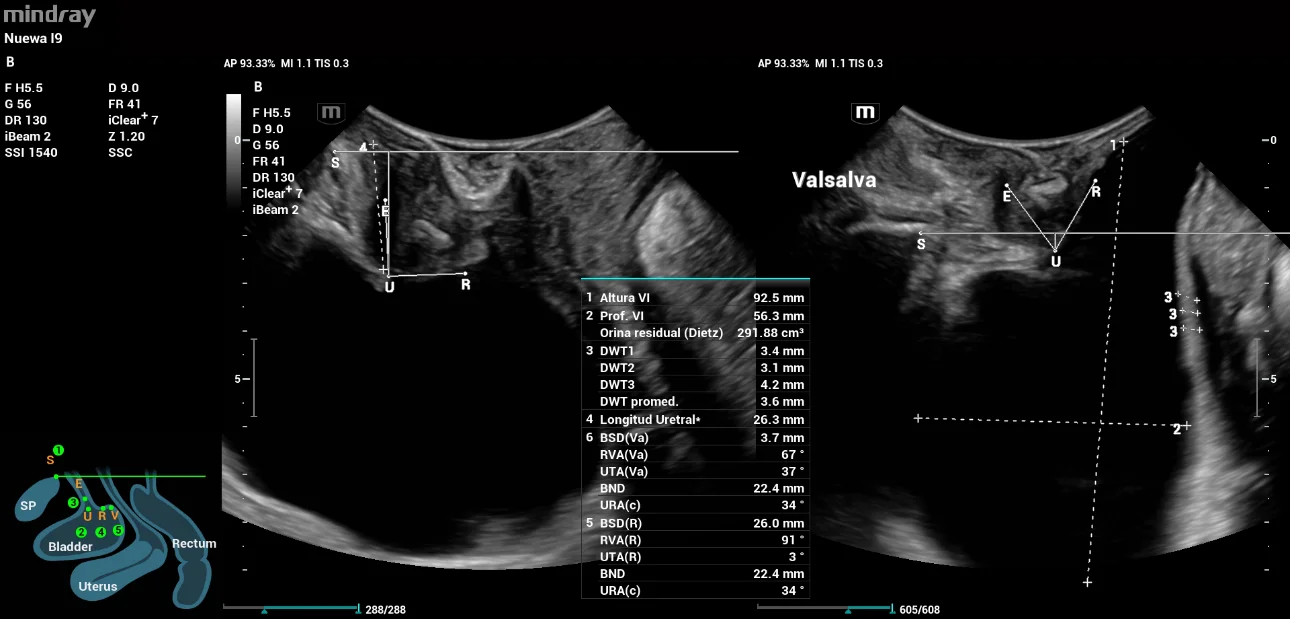

In the 2D scanning, we found the following results: Residual urine of 291ml, mean detrusor wall thickness (DWT) of 3.6mm within normal values. Bladder neck descent 22mm, α angle (URA) of 34°, β angle (RVA) of 67° (closed) and no presence of Funneling. Findings indicating Fixed urethra.

Figure 1: Evaluation of anterior compartment

During the evaluation at the periurethral level, an image suggestive of Sling with a horizontal vector (Trans obturator) was found, located in the middle third of the urethral; with the following measures:

Distance to the urethra (R) 2mm; distance to urethral meatus 16mm (R), 11mm (Val); distance to bladder neck 11mm (R), 8mm (Val), sling pubis GAP 18mm (R), 14mm (Val). No mesh presence. These findings are indicators of a Sling located at the level of the middle urethral third with measurements within the expected range.

Findings on 2D evaluation were as follows: Post-void residual 15 ml, increased DWT (5.9 mm). (Figure 7. a) Descent of bladder neck 14mm, α angle of 22°, β angle 93° (closed), and absence of funneling (Figure 7. b), indicative of FIXED URETHRA.

Figure 7: Evaluation of the anterior compartment 1. a) Urinary residue and DWT; 1. b) Descent of bladder neck and angles using Mindray Smart Pelvic

A periurethral evaluation was performed with an image suggestive of a MUS with a vertical vector (TVT), located at the junction of the middle and external urethral thirds (Figure 8).

The evaluation parameters of the MUS were: distance to the urethra 5mm (R); distance to the urethral meatus 4mm (R), 3mm (Val); distance to the bladder neck 16mm (R), 13mm (Val); pubic sling gap 17mm (R), 14mm (Val). No presence of prolapse mesh.